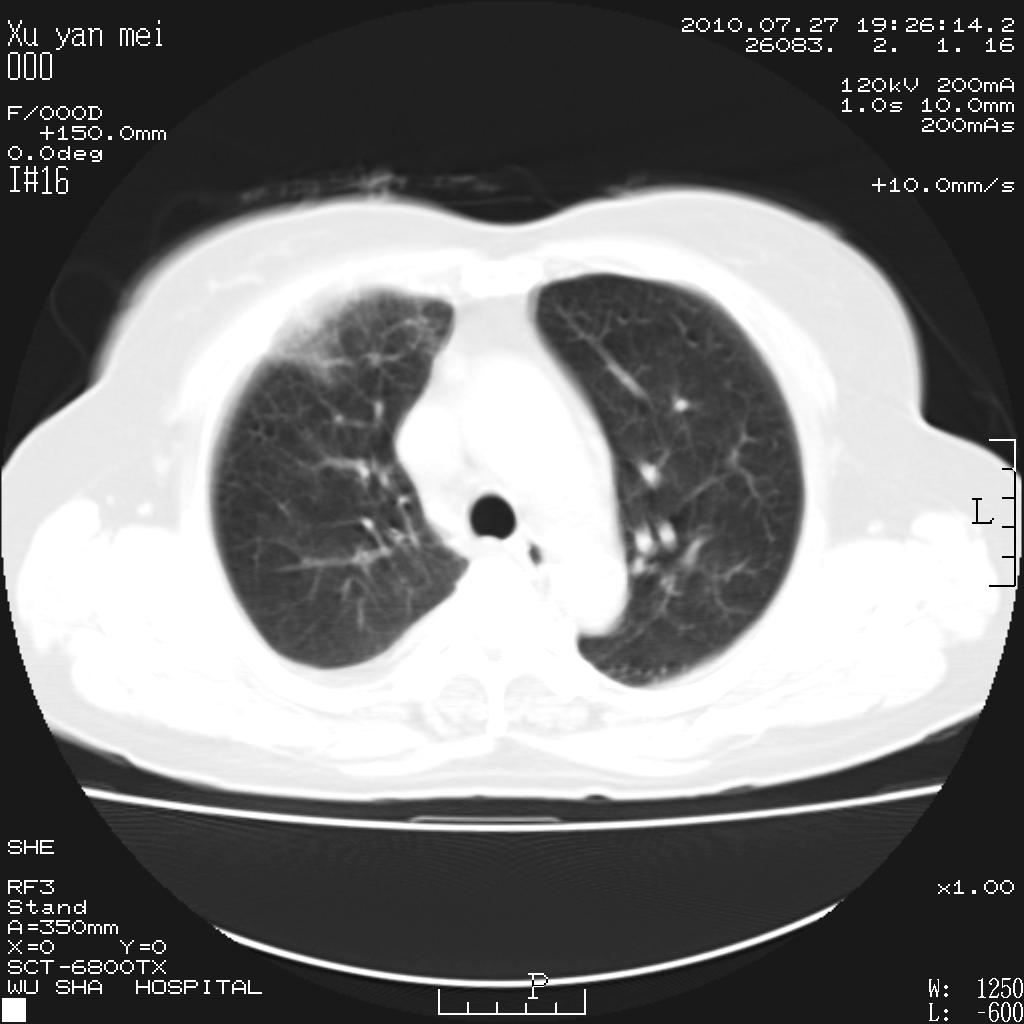

女,60岁,胸痛就诊,右肺结核?炎症?其它?(胸片右侧中上肺野确实看不到什么啊)

1)考虑两肺感染性病变;建议抗炎治疗后复查。2)双侧少量胸腔积液。

1)考虑两肺感染性病变;建议抗炎治疗后复查。2)右侧少量胸腔积液。

双肺炎症可能性大,建议抗炎后复查。右侧胸腔少量积液。双侧胸膜轻度增厚。

考虑两肺感染性病变;不除外肺栓;建议抗炎治疗后复查。